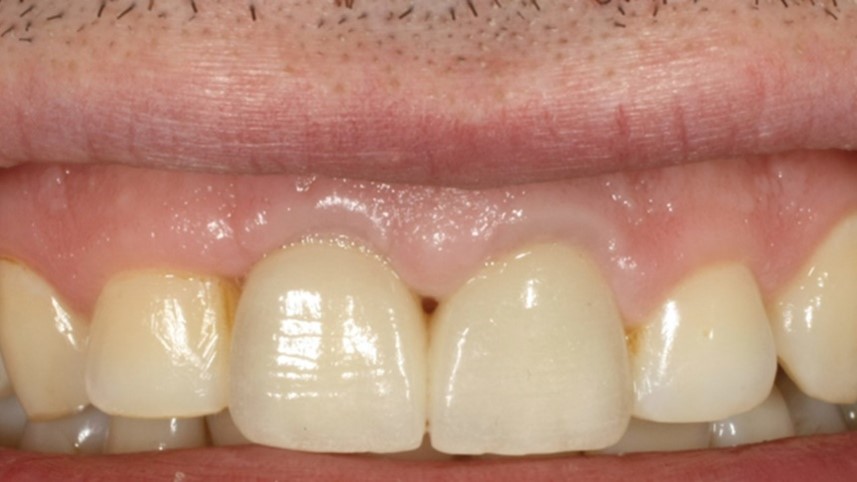

Il caso clinico del Professor Soardi illustra chiaramente i risultati estremamente interessanti che si riescono ad ottenere attraverso il protocollo Open Barrier Tecnique, attraverso un approccio minimamente invasivo ed utilizzando materiali e metodi testati. Come potrete vedere dal risultato finale anche una situazione così difficilmente recuperabile, in altissima zona estetica, può essere gestita e risolta ottimamente.

Tre momenti: al momento della chirurgia, dopo 1 settimana e dopo 4 settimane

Immagine clinica e radiografica al momento della rimozione della membrana